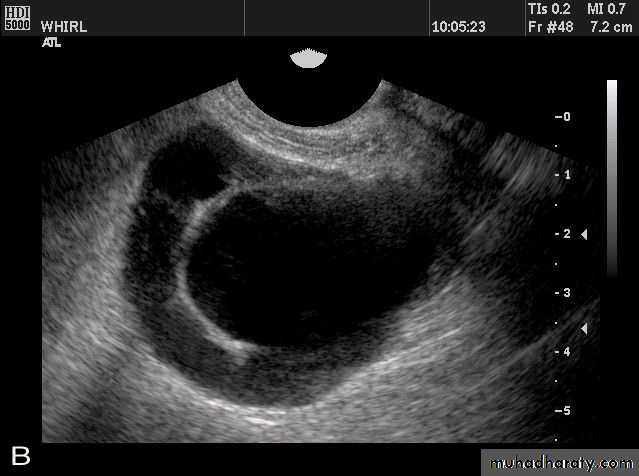

• POLYCYSTIC OVARY SYNDROME

Images from women with differing expressions of the four major subtypes of the metabolic syndrome associated with polycystic ovary syndrome (A–D). The images exhibit quite differing ultrasonographic appearances in the size and distribution of follicles within PCOS ovaries. A recent corpus luteum is clearly visible in the ovary in panel (D).